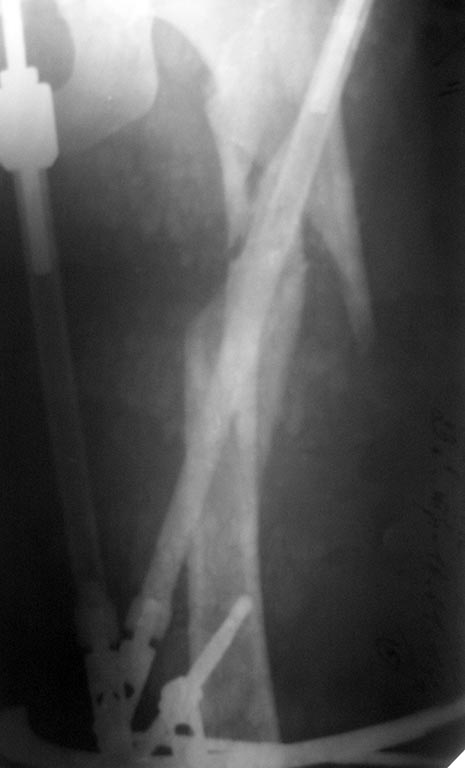

Пациентка К., 23 л., красивая девушка, уроженка одного из удаленных южных регионов России. Травма 31.12.13 в результате ДТП (столкновение а/машин). Находилась на лечении в нашем травматологическом отделении со следующим диагнозом: Сочетанная травма: ОЧМТ: Ушиб головного мозга легкой степени. Перелом передней стенки лобной пазухи со смещением отломков. Перелом латеральной стенки левой орбиты без смещения отломков. Ушибленные раны левого верхнего века. Ушиб левого легкого. Закрытое вертикально-нестабильное повреждение таза: трансфораминальный перелом крестца слева, частичный разрыв левого крестцово-подвздошного сочленения, вертикальный оскольчатый перелом крыла левой подвздошной кости со смещением отломков, поперечный перелом левой вертлужной впадины без смещения отломков. Закрытый многооскольчатый перелом левой бедренной кости в в/3 и с/3 со смещением отломков. Травматический шок II ст. При поступлении (снимок): АВФ типа "передняя рама" на кости таза с блоком на бедренную кость,ПХО ран. Лечение в условиях реанимации. По приказам о травмцентрах таких пациентов мы должныотправлять в травмцентр I уровня (областная больница). Однако с некоторых пор все разговорытам о переводе (стыдно за коллег) начинаются со слов: "А железку он(она) купит?" и озвучивается родственникам сумма с 4-5 нулями. Пациентка и ее родители к состоятельным не относятся. Поэтому дальнейшее лечение проходило у нас. Кости таза фиксированы канюлированными винтами и АВФ. Предполагался БИОС бедренной кости, однако из-за отсутствия в больнице современных имплантов(угадайте с 3-х раз- почему?)и средств у больной был выполнен 22.01.14 малоинвазивный остеосинтез проксимального отдела бедра чем Бог послал (каким-то чудом оказавшаяся у нас дистальная бедренная пластина "Деост", не б/у) (см. снимки)-критика принимается. П/операционный период гладкий. Выписана с рекомендацией начать нагрузку на конечность через 12 недель после операции. Убыла на малую родину. Дальнейшая связь поддерживалась по e-mail. Рекомендации она не соблюдала: нагрузку на ногу начала недели 3 назад. Сейчас беспокоят боли в одноименном коленном суставе, отека нет, болей в месте перелома нет, анализы в норме, незначительное ограничение движений в ТБС. По месту жительства выполнила КТ (снимки и описание в приложении). Местные коллеги утверждают, что необходимо сделать реостеосинтез, но сами не берутся. Вопрос больше от пациентки: "Делать ли повторную операцию сейчас, или некоторое время походить с полной нагрузкой и сделать контроль, а там решать?"

Что здесь хорошего? Репозиции нет, в боковой проекции угловое смещение. Пластина не прилегает к кости, и хотя она блокированная, но посмотрите – внизу пластина держится всего на одном блокирующем винте, два других не состоятельны, так как один недокручен(либо уже вышел из гнезда в пластине из за нестабильности), а другой закручен не перпендикулярно пластине (да и судя по боковой проекции, даже не в своё посадочное гнездо), следовательно, блокировка ненадёжна. Кортикальный (длинный) винт не всчёт, так как не притягивает пластину к кости. Ко всему ещё и два сломанных сверла… Вероятнее всего её ждёт перелом пластины и/или миграция фиксатора. На бедре особенно часто ломают пластины… Кроме блокированного интрамедуллярного остеосинтеза ( оптимальный способ), подошли бы: 1. Открытая репозиция, нормальный остеосинтез этой пластиной. 2. Открытая репозиция, остеосинтез четырёхгранным стержнем ( которых у всех в изобилии), дополненный серкляжной фиксацией отломков.

Я так понимаю "разрушить до основания, а затем..." Четырехгранный? При таком коротком проксимальном фрагменте??? Еще и серкляжи? Браво! В дистальном стоят 4 винта (хотя согласен, что пластина несколько коротковата). Угловых смещений я на этих снимках не увидел. А "ободрать" кость открытым методом, поимете проблемы. Михаил! Было бы неплохо посмотреть не КТ, а обычные рентгеновские снимки, на них мозоль видна лучше. И если уж переделывать (хотя я своего мнения не меняю), то только малоинвазивно ЗИМО у Александра Николаевича, тем более, что отозвался помочь.

Хорошо бы посмотреть свежие рентгеновские снимки. Это же апрельские. Может, действительно уже и так срастается.